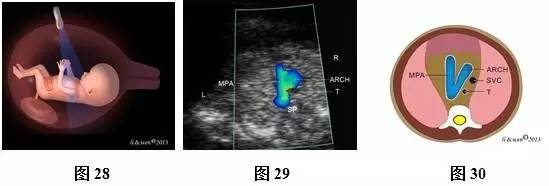

超声扫查方法:声束从心尖部进入,在膈肌稍上方横切胸腔(图25),即获得心尖四腔心切面(图26,27);声束平面向胎儿头侧偏斜(图28),即可获得三血管气管切面(threevessels and trachea view,3VT,图29,30)图像。

标准切面判断标准:四腔心切面显示心脏四个腔室,可见二、三尖瓣启闭运动。3VT切面显示从左向右依次显示肺动脉、主动脉弓和上腔静脉,肺动脉和主动脉弓排列呈“V”形,两者血流方向相同。彩色多普勒血流成像对这些结构显示更清楚。

主要观察内容:四腔心切面主要观察心脏位置,心尖指向,心脏轴,左、右房室大小,房室瓣情况等。3VT切面主要观察肺动脉、主动脉弓、上静脉排列关系,血管数目,血管径线,血流方向等。

注:LV为左心室;RV为右心室;LA为左心房;RA为右心房;DAO为降主动脉;MPA为主肺动脉;ARCH为主动脉弓;T为气管;SVC为上腔静脉;R为右侧;L为左侧

图25~30 11~13+6孕周胎儿心脏扫查方法、观察内容及声像图及模式图。图25四腔心切面扫查模式图;图26、27四腔心切面彩色多普勒声像图及模式图;图28 3VT切面扫查模式图;图29、30 3VT彩色多普勒声像图及模式图